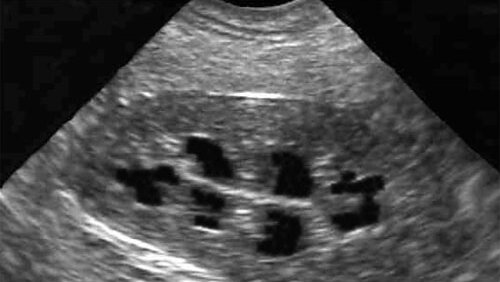

Нефросклероз

Что же такое нефросклероз? Нефросклероз-(синоним: «сморщенная почка») — патологическое состояние, при котором ткань почки заменяется соединительной тканью, а сама почка уменьшается в размерах («сморщивается»), при этом нарушаются её функции вплоть до полного прекращения работы почки...